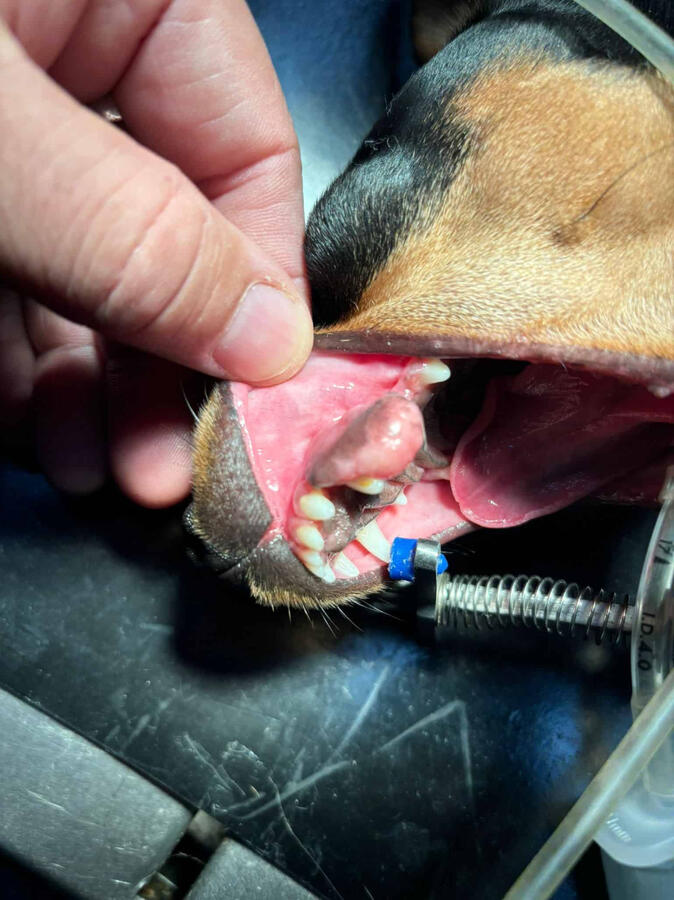

Profesional veterinarian in South Tenerife. Located in El Porís de Abona, and working for more than 24 years.We take care of your pet with a humane, consistent, warm, and close approach. Our main mission is to keep them healthy, focusing on preventing possible animal diseases and, in case of illness, treating them responsibly, affectionately, and professionally.We only attend by appointment. We do not offer emergency services or hospitalization.

24 years of experience as a veterinarian, specializing in surgery and anesthesia. A member from the very beginning of the emergency veterinary team - a unique body in the world - coordinated with Cruz Roja, and El Cabildo de Tenerife. Collaborator for 18 years with over 15 Animal Protection Associations, such as ASFA, K9 Chafiras Tenerife, Burros Felices de El Hierro, Verein Hilfe Fur Tiere, Pro Animal Gomera, the club de la huella... Among others.

Services

Consultation 40€Rabies vaccine 20€Digital radiography 35€Fast basic ultrasound 30€Canine multivalent vaccine 28€Feline multivalent/leukemia vaccine 28€Neutering male dog (<15kg) 160€(15-30kg) **180€ (>30kg) 195€

80€ Neutering male cat145€ Neutering female cat200€ Export Certificate CEXGAN25€ Filarias Test45€ Test x 4 (fil, Ehrlich, Lyme, Leish)28€ Felv Fiv Test45€ Blood Chemistry 14 parameters